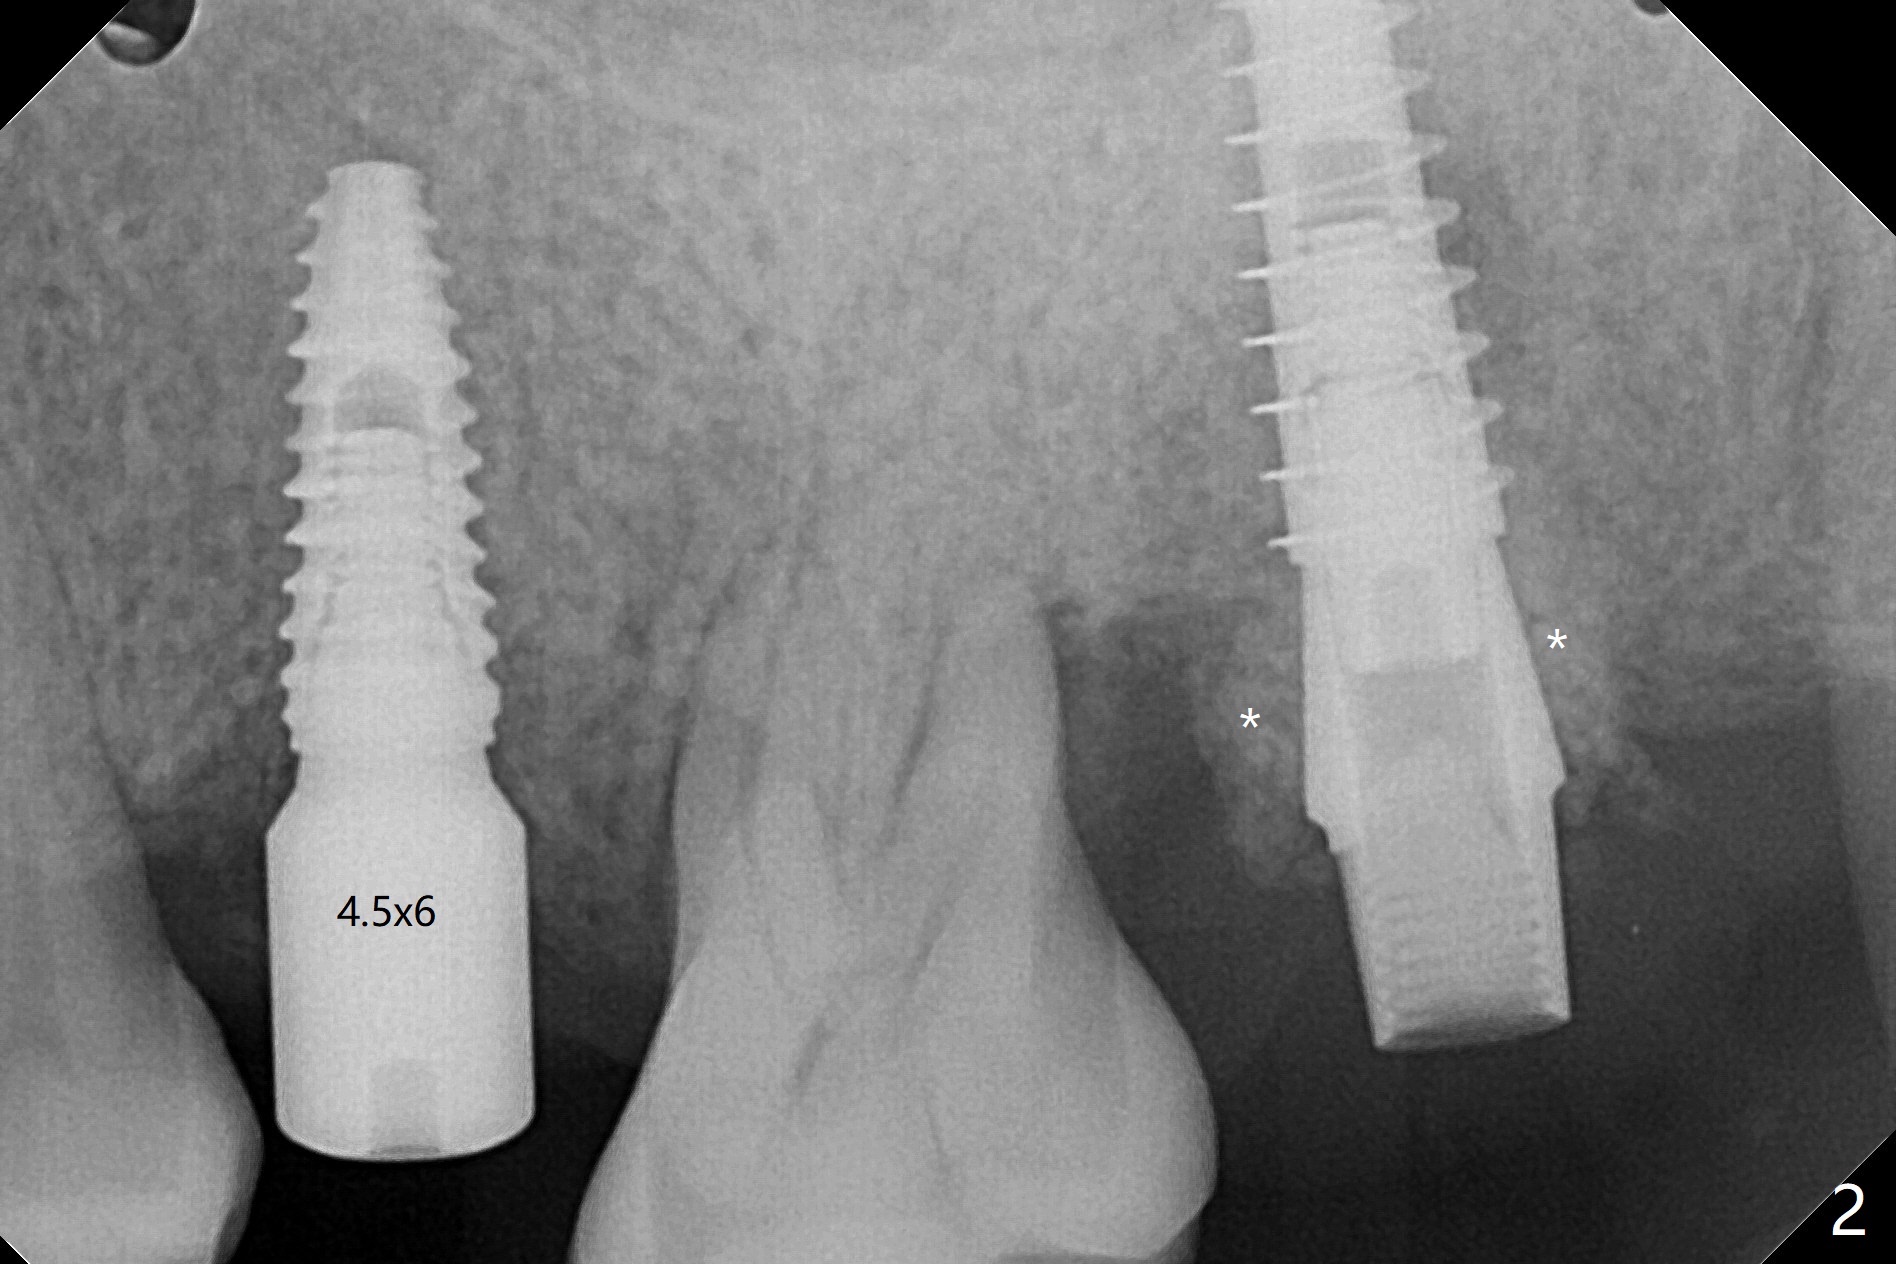

左上5延期植体扭力很高(50 Ncm,图一),而7(即刻)低(~15 Ncm),放置粘性骨粉后(图二:*),制作临时牙冠,长植体尚未穿过上颌窦底板(图三:红虚线)。